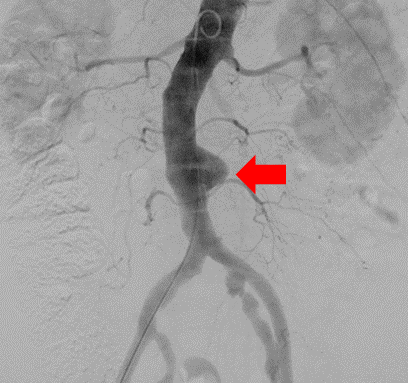

【症例5:大動脈瘤に対するステントグラフト内挿術】

治療前

腹部の動脈に大きな瘤ができている。(赤矢印)

治療後

瘤に流れる血流を遮断し、瘤が消失している。